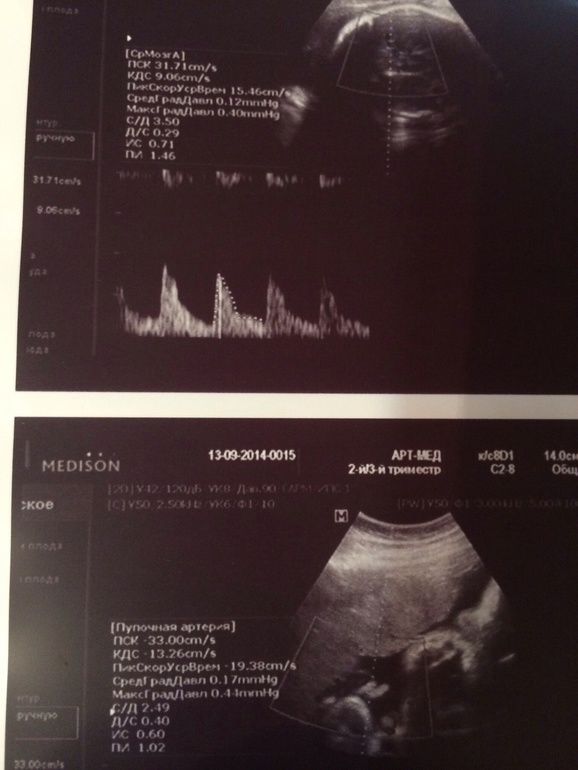

Маленькие изображения. Скинь мне в ВК или сюда в ЛС, я попробую разглядеть.На втором снимке явно какая-то волновая пульсация (то есть, как раз кровоток), но что это за артерия или что — не видно.

Я еще поняла что в таких случаях на доплер смотрят?! Он в норме! И кровоток в норме!

В норме должны быть минимум 3 параметра: структура плаценты, степень зрелости и сам по себе допплер. У тебя же, получается в норме только 1 параметр — допплер. И допплер не покажет тебе на сколько хорошо доставляется именно кислород к плоду. Это показывает, как правило, состояние плаценты.

Вот еще есть Я тоже внимание обратила, что она размер не указала!!